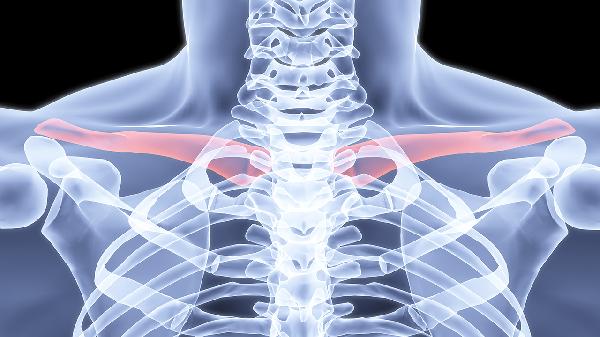

锁骨骨折多数情况下无需手术治疗。治疗方案选择主要取决于骨折类型、移位程度、患者年龄等因素,保守治疗方式包括八字绷带固定、锁骨带固定、限制活动、物理治疗及药物镇痛。

无移位或轻度移位的锁骨中段骨折通常选择保守治疗。这类骨折稳定性较好,通过外固定可达到自然愈合,愈合周期约6-8周。若为粉碎性骨折或伴有血管神经损伤,则需手术干预。

骨折端重叠小于2厘米或成角小于30度时优先考虑非手术治疗。严重移位可能导致畸形愈合影响肩关节功能,此时需手术复位内固定。儿童锁骨骨折因骨膜较厚,即使明显移位也多可保守治疗。